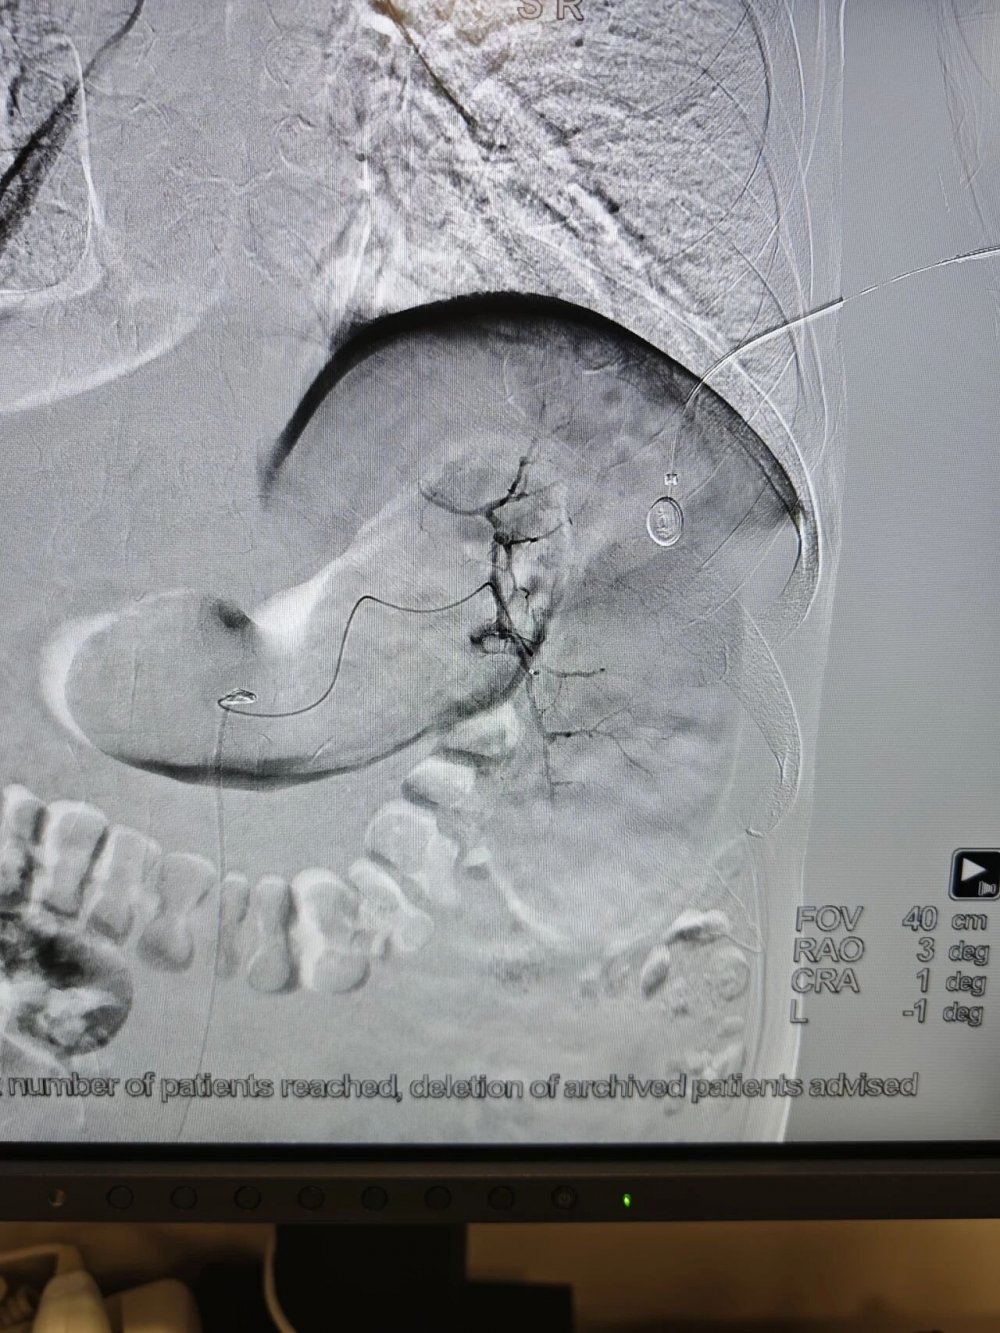

手术全程在数字减影血管造影(DSA)高清影像实时监控下开展,全程可视化操作,精准、安全、可控。

术中,介入医学科负责人卜高峰通过微细导管沿血管通路精准送达脾动脉主干,精准定位异常增生、过度亢进的病变脾组织血管分支,注入专用栓塞颗粒,选择性阻断脾脏病变区域血供,让亢进的脾组织逐步缺血萎缩,从根源解决脾功能亢进问题。

手术中,导管精准抵达脾动脉位置,清晰显示脾脏血管供血形态,为后续栓塞操作提供精准定位

栓塞过程中,通过导管向病变脾组织血管注入栓塞颗粒,精准阻断异常供血,最大程度保留正常脾组织。